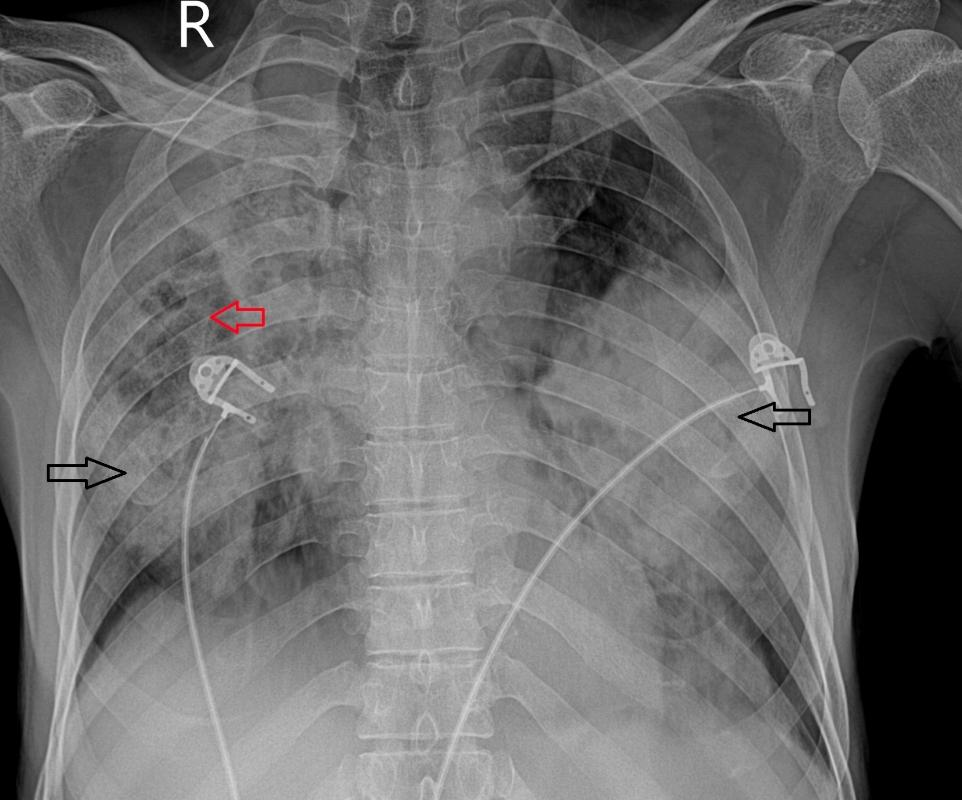

PA胸片示双肺大面积融合实变,右中部实变内可见少量透亮区。胸部CT平扫显示双肺广泛实变,其间有磨玻璃影、间隔增厚及多发小囊性/空洞区。部分实变显示内部低密度区(衰减值范围为15-25 HU)。无

图1 PA胸片示双侧肺实变(黑色箭头),右中部可见多发囊性透亮区(红色箭头)。